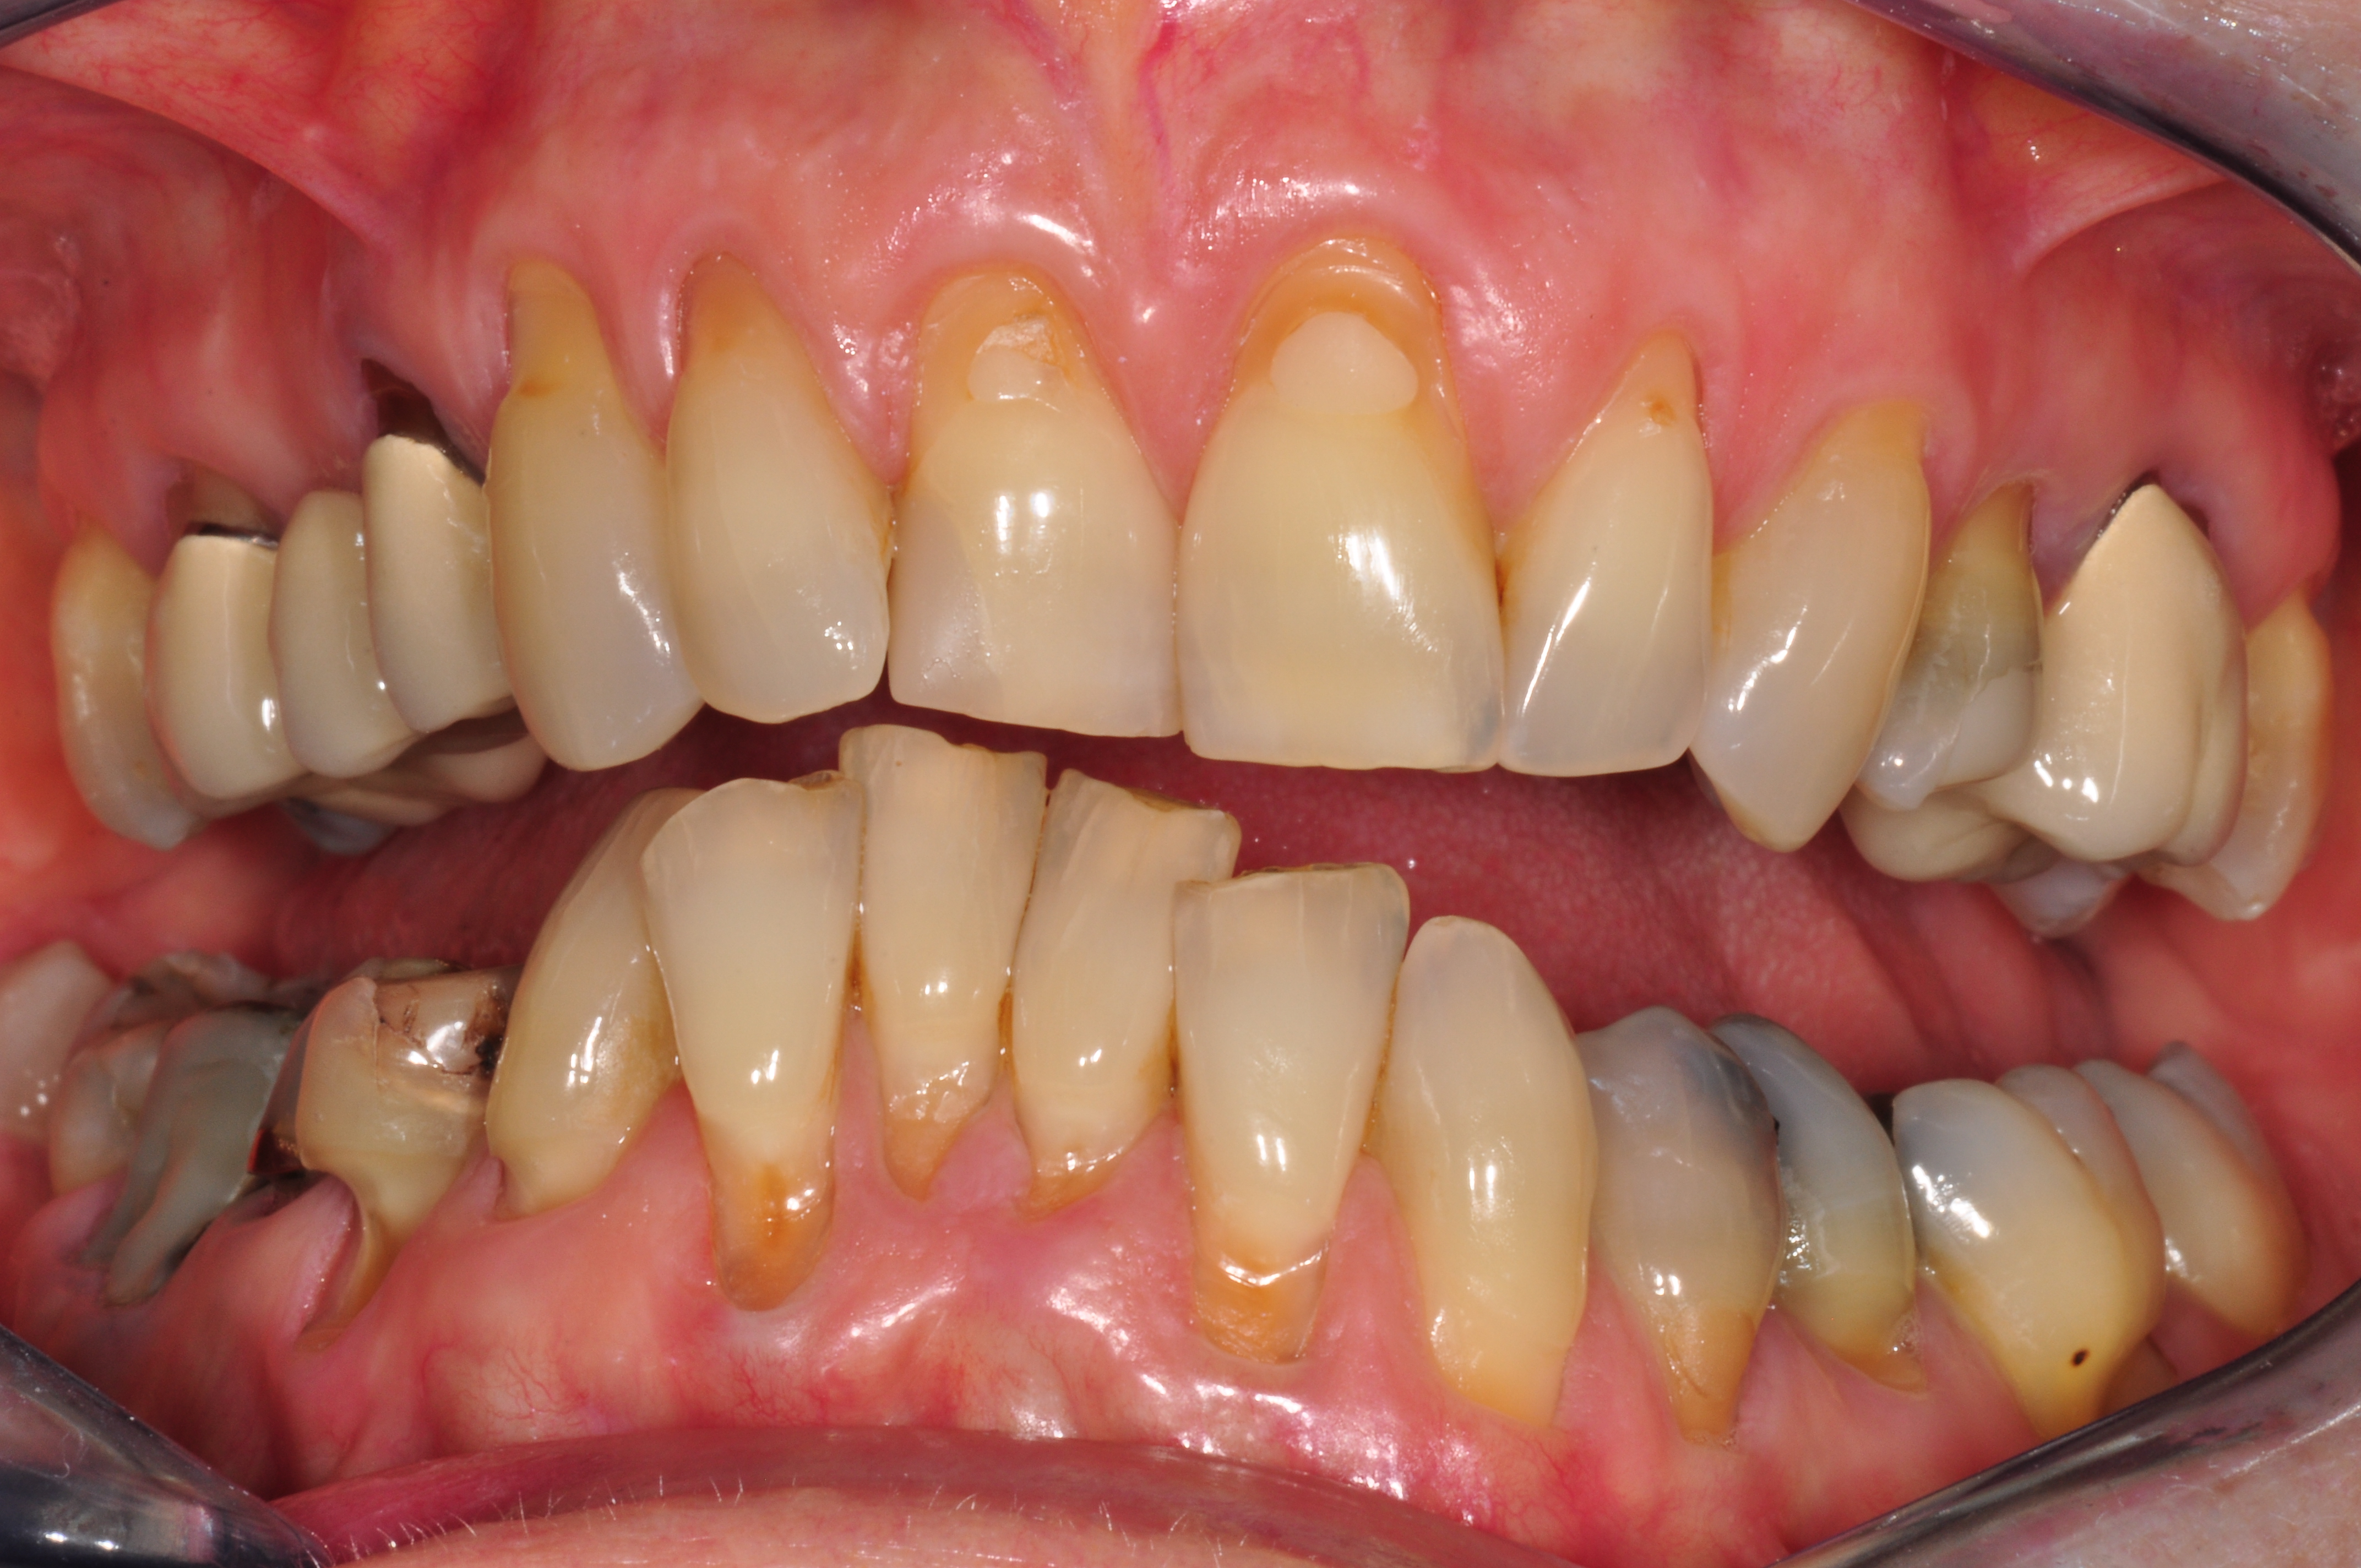

Unbefriedigende Ästhetik, vor allem aber Entzündungen im Knochen und eine massive Parodontitis mit bereits gelockerten Zähnen

Vorher: Unbefriedigende Ästhetik, vor allem aber Entzündungen im Knochen und eine massive Parodontitis mit bereits gelockerten Zähnen

Gesamtbehandlung in Sedierung: die Seitenzähne wurden durch Keramik-Implantate (Zahnentfernungen und Sofortimplantation) mit Knochenaufbau ersetzt; anschließend Gesamtüberkronung aus Vollkeramik mit Optimierung der Ästhetik

Nachher: Gesamtbehandlung in Sedierung: die Seitenzähne wurden durch Keramik-Implantate (Zahnentfernungen und Sofortimplantation) mit Knochenaufbau ersetzt; anschließend Gesamtüberkronung aus Vollkeramik mit Optimierung der Ästhetik